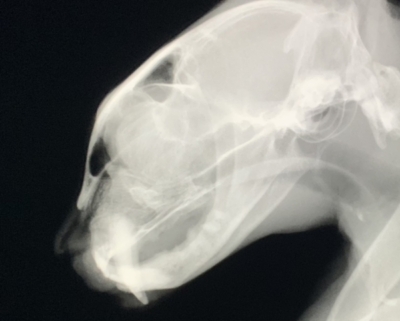

他院で抜歯したが治らないという口内炎の猫ちゃん。初日、歯科用レントゲンでなくとも麻酔をかけず一般的な頭部のレントゲン撮影でも歯の根っこが下顎に残っているのがわかった。